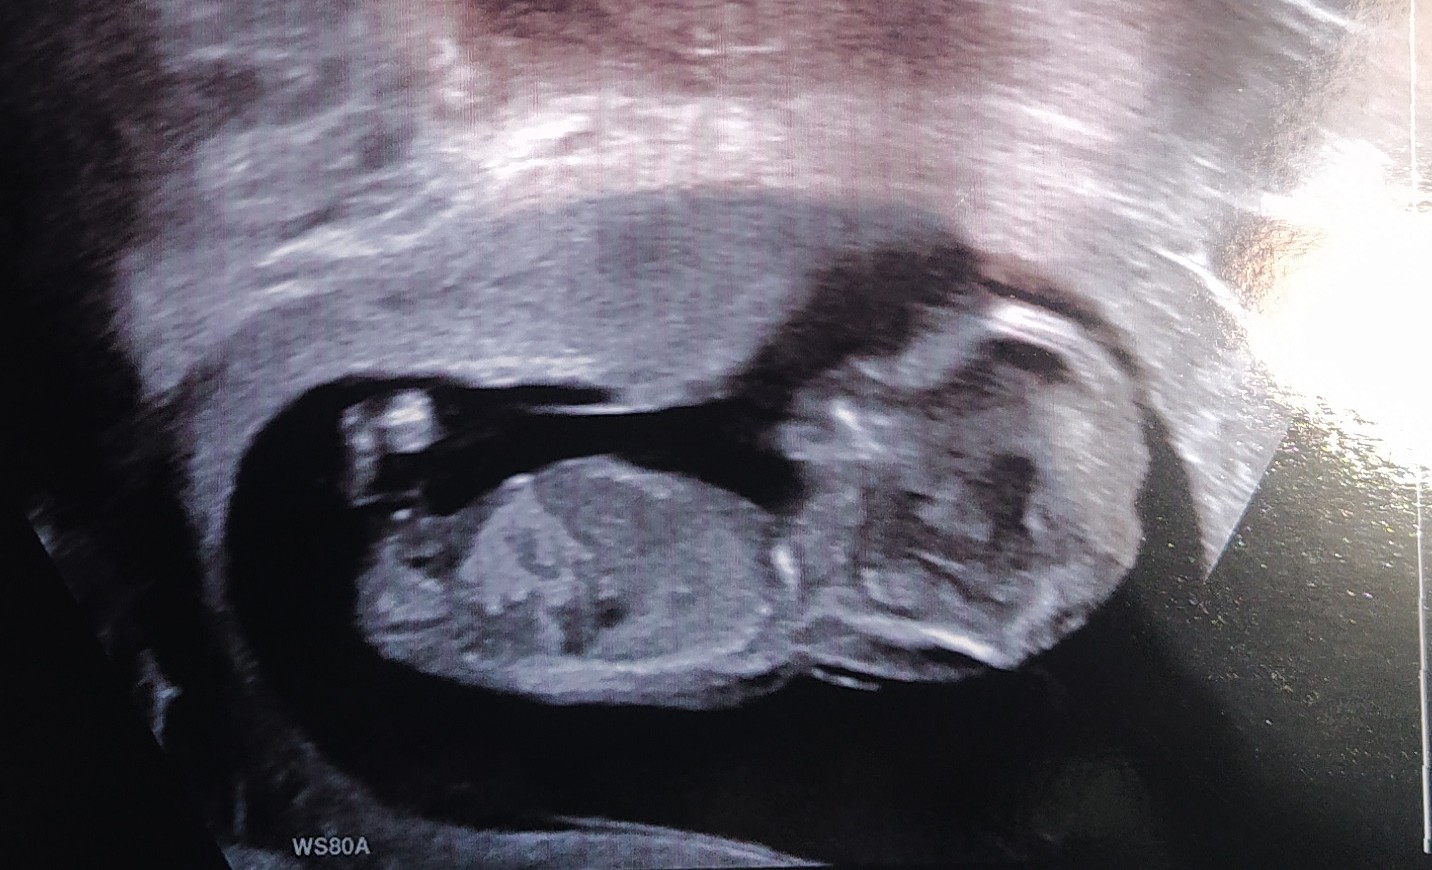

@rennye a co ady prosím?

@almidrob2539 To je nějaká kustka, kazdopadne kávové zrno to určitě není. To bývá vidět přímo mezi nozkama, tady jsou záda. 🙂 na fotce to bohužel nejde vidět. A pokud neviděl doktor, my tady těžko uvidíme.

@almidrob2539 To je pořád ta samá fotka, ale zvětšená. Holka to být může, je to více pravděpodobné, ale jistá bych si tím nebyla, je to špatně vidět. Takové fotky mám i od kluků 😂.